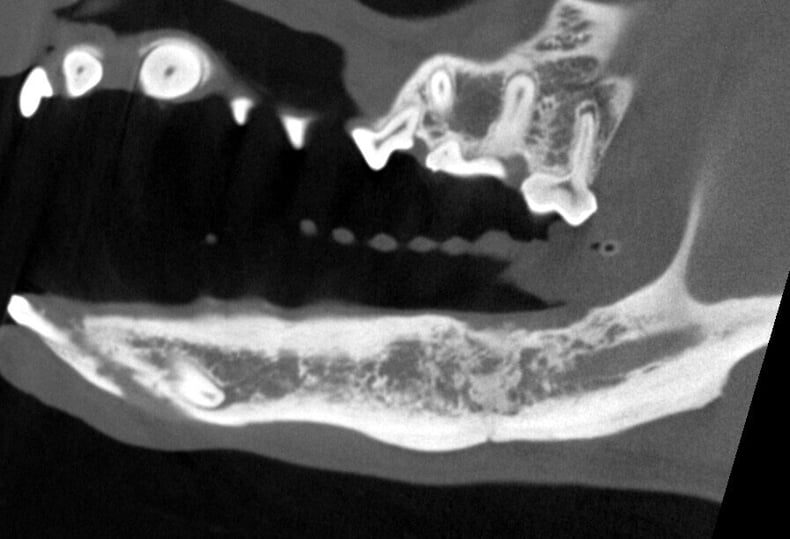

The internal structure of the affected tooth showed disease at the root tips, leading to infection. This infection had spread into the mandibular canal and affected nearby teeth. Although there was reactive bony proliferation on the ventral aspect, significant bone loss was also noted, which posed a risk for a pathological mandibular fracture.

Below: CT Cross Section of Disease